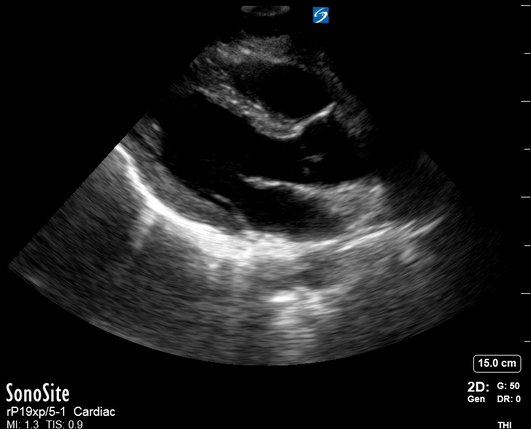

Equality: is the RV dilated or significantly impaired?

Normally, the RV is a low-pressure, thin-walled, high-compliance chamber that wraps anteriorly around the muscular, cone-shaped LV. The normal RV : LV diameter ratio is 0.6 : 1.

When the pulmonary artery pressure rises, the RV will dilate, altering the normal RV:LV ratio. Although sacrificing sensitivity, the use of equality (1:1 ratio) as a cutoff can achieve a specific estimation of RV strain. If imaged correctly by a trained operator, the presence of an RV:LV ratio > 1 is highly specific for RV strain.

RV dilation can be acute, chronic, or acute-on-chronic. However, in patients presenting with undifferentiated chest pain, shortness of breath, hypotension or syncope, the presence of any RV dilation should raise suspicion for acute pulmonary embolism (PE). Furthermore, in a patient in shock, the presence of RV strain may signal the need for aggressive therapy – emergency thrombolysis.

THE VIEWS

The A4C view provides an accurate chamber size comparison. However, achieving a proper A4C view (avoiding foreshortening or ballooning, and visualising the four chambers with a vertically oriented interventricular septum) can be a challenging exercise of image acquisition. Additionally, the PSAX view at the level of the papillary muscles shows both LV and RV side by side and is useful to assess function and size. When RV pressure is high, the septum will be pushed and flattened towards the LV, resulting in the characteristic “D-shaped” LV or “D sign”.

PITFALLS

When comparing size, beware of correct image acquisition, as oblique planes lead to misinterpreting the RV:LV ratio. For apical views be sure to slide the probe sufficiently laterally on the chest wall so that it lies over the true apex. Also, be sure to obtain a real horizontal plane, avoiding foreshortening (ballooning). For the PLAX view it is useful to fan through the heart’s long axis, making sure that LV visualization is maximized relative to the RV. Furthermore, an understanding of probe placement and marker orientation conventions is fundamental. If inadvertently scanning in reverse orientation, the normally larger LV could be mistaken for an abnormally enlarged RV.